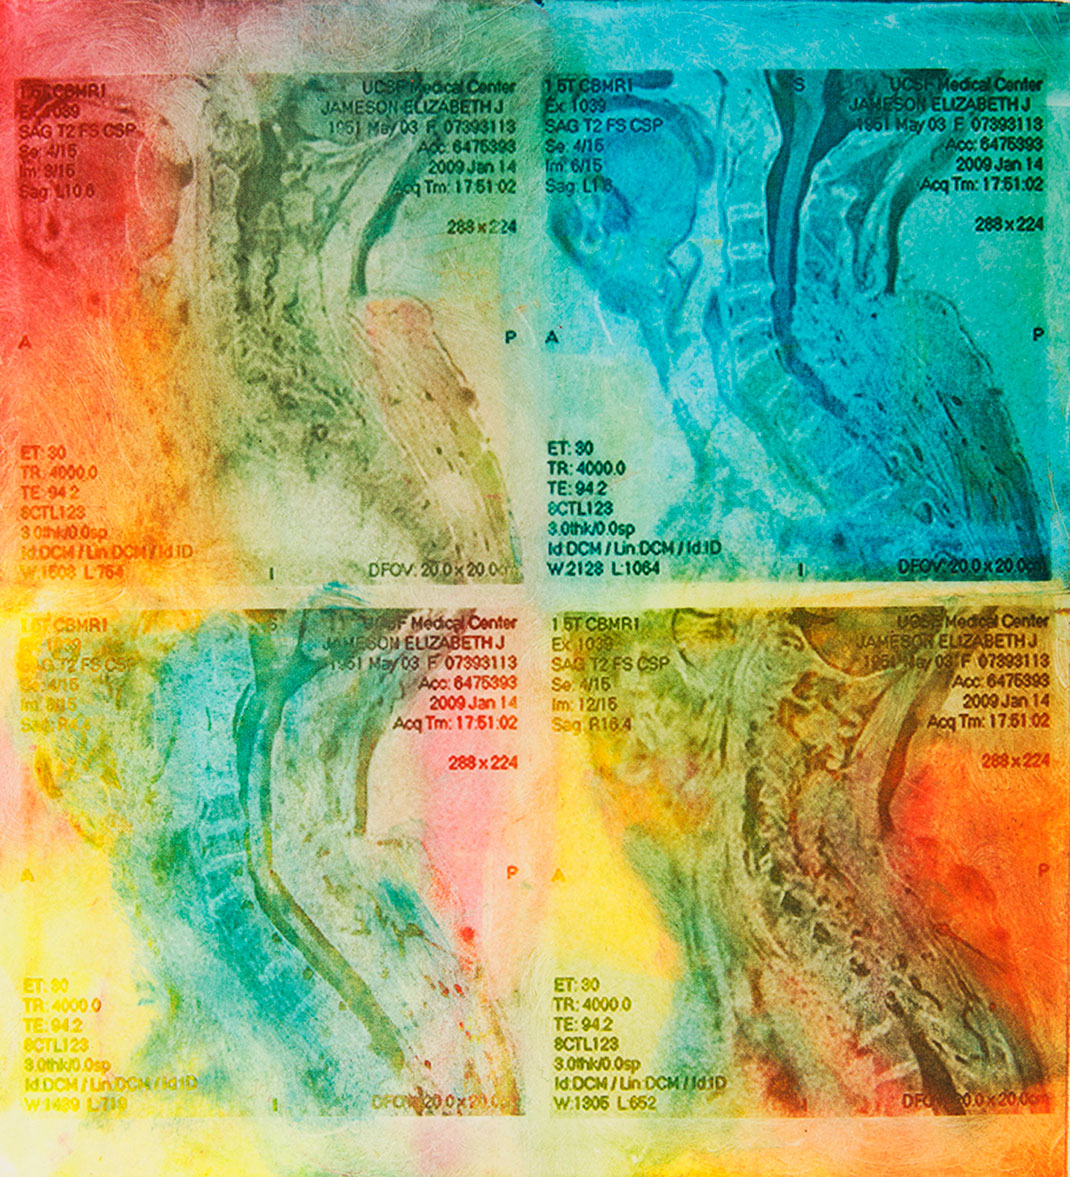

En 1991, elle découvre qu’elle est atteinte de sclérose en plaques. « J’étais en train de jouer avec mes enfants dans un parc. Je n’ai pas eu mal, je n’ai eu aucun signe de quoi que ce soit, j’ai juste découvert que je ne pouvais plus parler. La semaine suivante, les chirurgiens m’ont enlevé une partie du cerveau pour découvrir la source de mon aphasie. Le diagnostic était clair, j’étais atteinte de sclérose en plaques. A partir de ce moment-là, j’ai passé de nombreuses heures dans l’appareil IRM », explique-t-elle.

Elle trouve alors sa source d’inspiration dans sa maladie à travers ses IRMs. « Mes nombreux traitements m’ont donné envie de réinterpréter l’imagerie médicale. Les patients, souvent anxieux, ne voient que laideur et effroi dans les pixels noirs et gris des IRMs. J’ai alors ressenti le besoin vital de les utiliser pour montrer les merveilles et la beauté de nos cerveaux, y compris ceux souffrant d’une maladie. Je veux guérir les patients de la peur de regarder leurs IRMs », s’émeut Elizabeth.

En réutilisant ses scanners, Elizabeth Jameson cherche à insuffler des émotions et des sentiments dans la froideur technologique. Pour cela, elle utilise de nombreux supports : la peinture sur soie ou encore des impressions à partir de gravures sur cuivre ou sur plaque solaire. Ensuite, elle renforce la couleur de ses images grâce à de la peinture, des crayons ou du pastel sec. Le résultat offre une collection brillante, colorée, pleine d’émotion et de symbole.

Maintenant tétraplégique, Elizabeth crée avec l’aide d’un assistant. Selon elle, ses impressions ne sont pas qu’un moyen de faire la chronique des changements de son cerveau, qu’elle qualifie d’« organe le plus sacré ». Son travail est également un moyen de devenir plus familière avec ces changements, pour les rendre moins terrifiants. « Mon art est composé à 90 % de mon cerveau, tout simplement parce que je suis mon cerveau », conclut-elle.